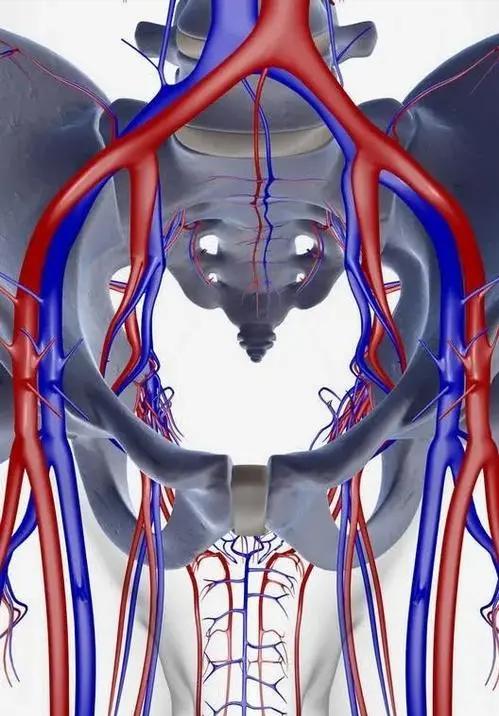

而骨盆后环主要是指骶髂关节,骶髂关节是人体最重要的关节之一,不仅是组成骨盆后环的重要结构,还在人体重力的传递中起到了重要的作用。

骶髂关节关节面扁平,是由髂骨以及骶骨耳状面组成,彼此对合紧密,关节囊紧张,并且其周围有许多强韧的韧带加强,比如:骶髂前韧带、骶髂后韧带、以及骨间韧带等。

其关节腔狭小的裂隙状, 因而骶髂关节是一种微动关节,这样的结构有利于支持体重和传递重力,在老年人中,骶髂关节部分关节面融合,关节活动基本上消失。

在影像学中,骶髂关节通常被用来评价骨盆损伤稳定性是否遭到破坏,骶髂关节是否有移位是其判断标准。